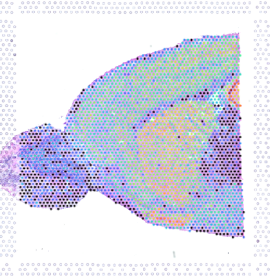

圖 基于 spot 的 cluster 分類(t-sne 圖)和 cluster 在切片上的分布

圖 海馬 marker HCPA 基因在切片上的表達分布(紅色區域表達量高)

圖 根據病理信息選擇特定區域進行分析(或者多個區域進行比較分析)

圖 不同細胞類群映射到切片上的結果